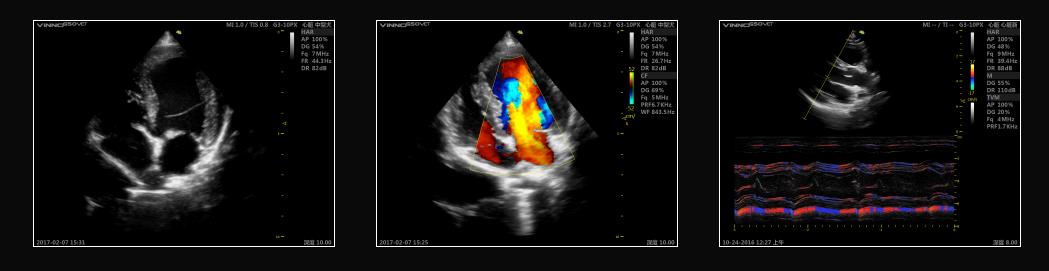

VINNO G55 VET

Najwyższa jakość obrazowania ultrasonografu weterynaryjnego.

Doskonała jakość dopplera w badaniach naczyniowych:

Ultrasonograf weterynaryjny VINNO G55 VET cechuje najwyższa jakość i czułość dopplera kolorowego wśród urządzeń dostępnych na rynku weterynaryjnym:

• niezwykle czuły przepływ koloru (CFI/ PDI)

• ostre i czyste spektrum dopplera fali pulsacyjnej, odbierające wysoką prędkość

• doskonałe obrazowanie w trybie Triplex

• automatyczne śledzenie spektrum w PW/CW

Ultrasonograf weterynaryjny VINNO G55 VET cechuje doskonała jakość wyświetlanego obrazu. W urządzeniu zastosowano innowacyjną platformę RF, która odczytuje szerszy zakres sygnałów. Wyświetlany obraz jest bardziej wyraźny i posiada wyższą, niż standardowo, rozdzielczość.

Nowa jakość badań kardiologicznych – technologia Single Crystal

Single Crystal = WYSOKA CZUŁOŚĆ + SZEROKIE PASMO + CZYSTY OBRAZ w obrazie B-Mode i Dopplerze kolorowym. Aparat ultrasonograficzny VINNO G55 VET wyposażony jest w specjalną głowicę sektorową do badań echokardiograficznych, dedykowaną technologii Single Crystal. Zamiast konwencjonalnych złożonych piezoelektrycznych elementów, ultrasonograf weterynaryjny wykorzystuje pojedyncze kryształy (Single Crystal), emitując jednolitą transmisję Tx. Sprawia to, że fale ultradźwiękowe mogą dotrzeć głębiej w strukturę tkanki oraz pod różnymi kątami. Lepsza penetracja tkanek w połączeniu z doskonałą jakością obrazowania pozwala na uzyskanie najdokładniejszych pomiarów już za pierwszym badaniem!